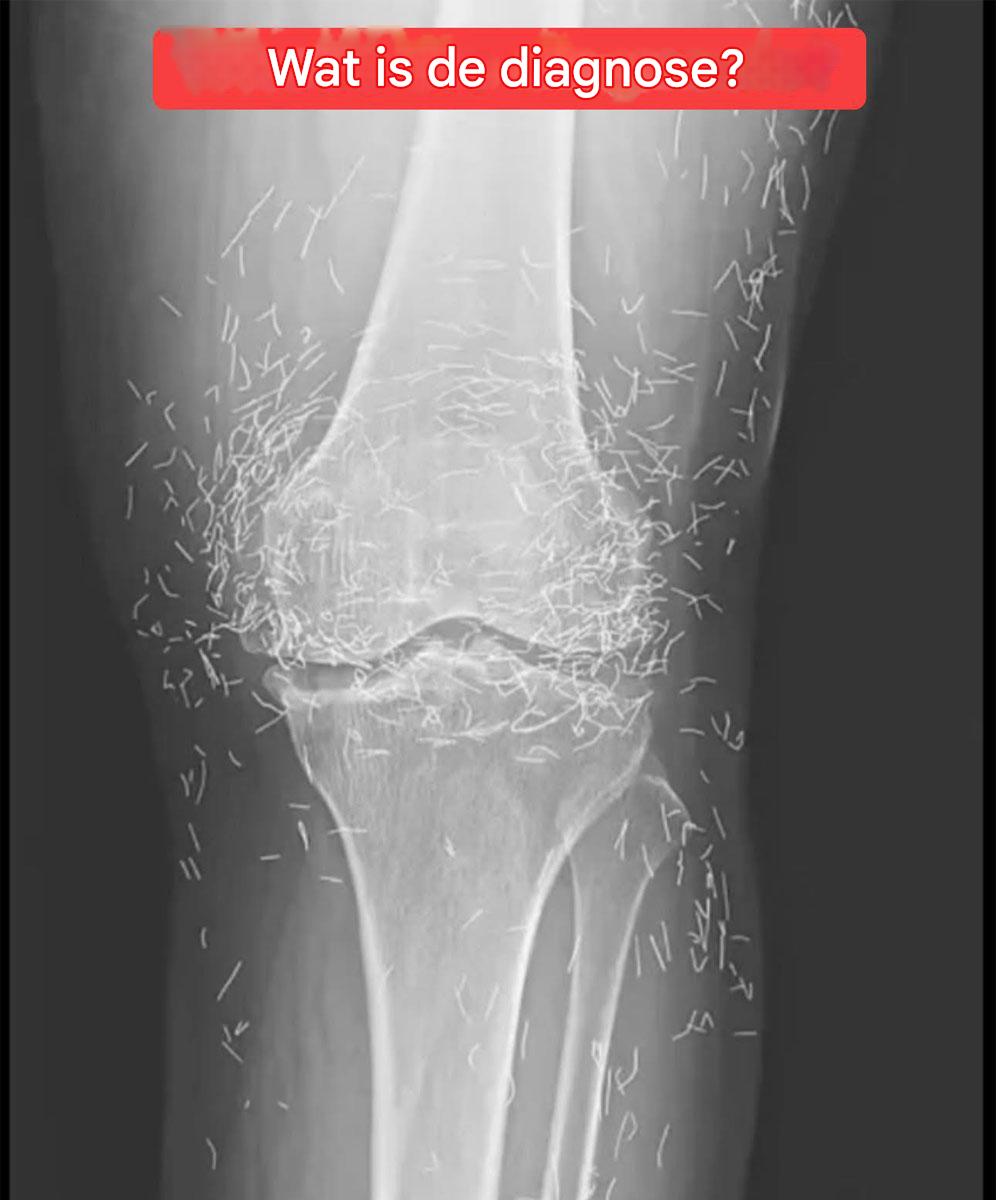

Röntgenfoto onthult honderden gouden naalden in knieën van vrouw

Toen artsen een röntgenfoto van de knieën van een oudere vrouw met ernstige gewrichtspijn onderzochten, ontdekten ze een goudmijn: honderden kleine gouden acupunctuurnaaldjes die in haar weefsel waren achtergebleven. De 65-jarige Zuid-Koreaanse vrouw had eerder de diagnose artrose gekregen, een aandoening waarbij het kraakbeen en de botten in haar gewrichten aftakelen, wat pijn en stijfheid … Lire plus